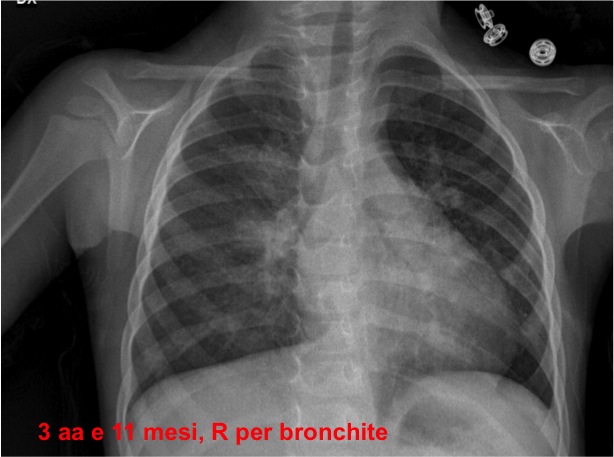

Per il quadro di anemia sideropenica associata a dispnea e infezioni ricorrenti delle basse vie aeree, nel forte sospetto di alveolite emorragica, abbiamo riguardato la storia radiologica della bambina: numerosi Rx torace che mostrano opacit� bilaterale diffusa e aumentata trama interstiziale, sia durante episodi di broncopolmonite che in benessere (Figure 1-4).

Figura 4. Rx effettuata a 3 anni e 11 mesi, durante un ricovero per bronchite.